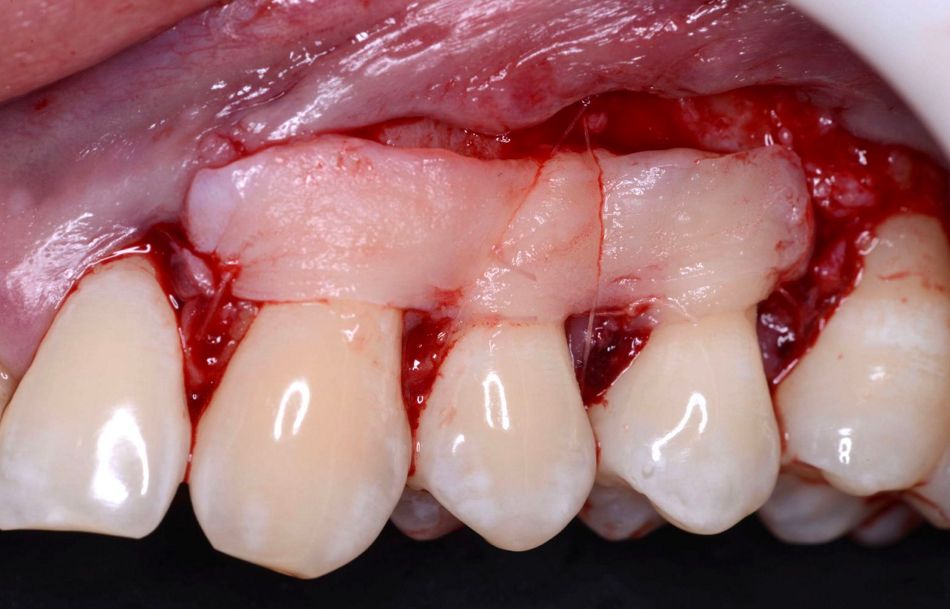

Surgical procedure

The following clinical measurements were taken before surgical procedures: marginal gingival recession (REC), measured from the cemento-enamel junction (CEJ) to the most apical extension of gingival margin, probing depth (PD) and clinical attachment level (CAL), measured from the CEJ to the bottom of the gingival sulcus.

The surgery was done under local anesthesia. An envelope flap was raised with a split-full-split approach. The root surfaces were mechanically treated with the use of curettes and chemically treated with Straumann Prefgel® and Straumann Emdogain®. On the left-hand side, after preparation of the envelope flap, the autologous connective tissue graft was positioned to cover the recessions.

Sutures were performed to accomplish a precise adaptation of the buccal flap on the exposed root surfaces.

On the right-hand side, same flap approach was carried out but mucoderm(R) was used as a graft.

To facilitate handling of the matrix, the hydration procedure is very important. In this case, blood from the flap preparation was used and small perforations were made. mucoderm(R) was cut to shape with a pair of scissors to adapt it to the recession defect. mucoderm(R) was fixed with resorbable sutures, whereas the flap was closed using non-resorbable suture material.